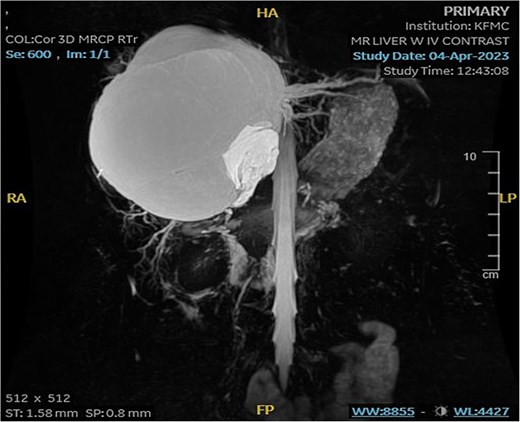

Mild splenomegaly (13.4 cm) with no focal lesions was noted, which exerted a mass effect on the patent hepatic vasculature. No osseous lesions or lymphadenopathies were identified. Three smaller bright T2 signal intensity lesions that did not enhance on post-contrast scanning were seen in segments 7 and 6, with measurements 0.2 × 0.1 cm, 0.7 × 0.7 cm, and 0.9 × 0.4 cm, respectively. The consistency of the cyst is evident from Fig. 3.

MRI of the liver: Demonstrating smaller bright T2 signal intensity lesions without post-contrast enhancement were observed in segment 7 and segment 6, consistent with cysts.